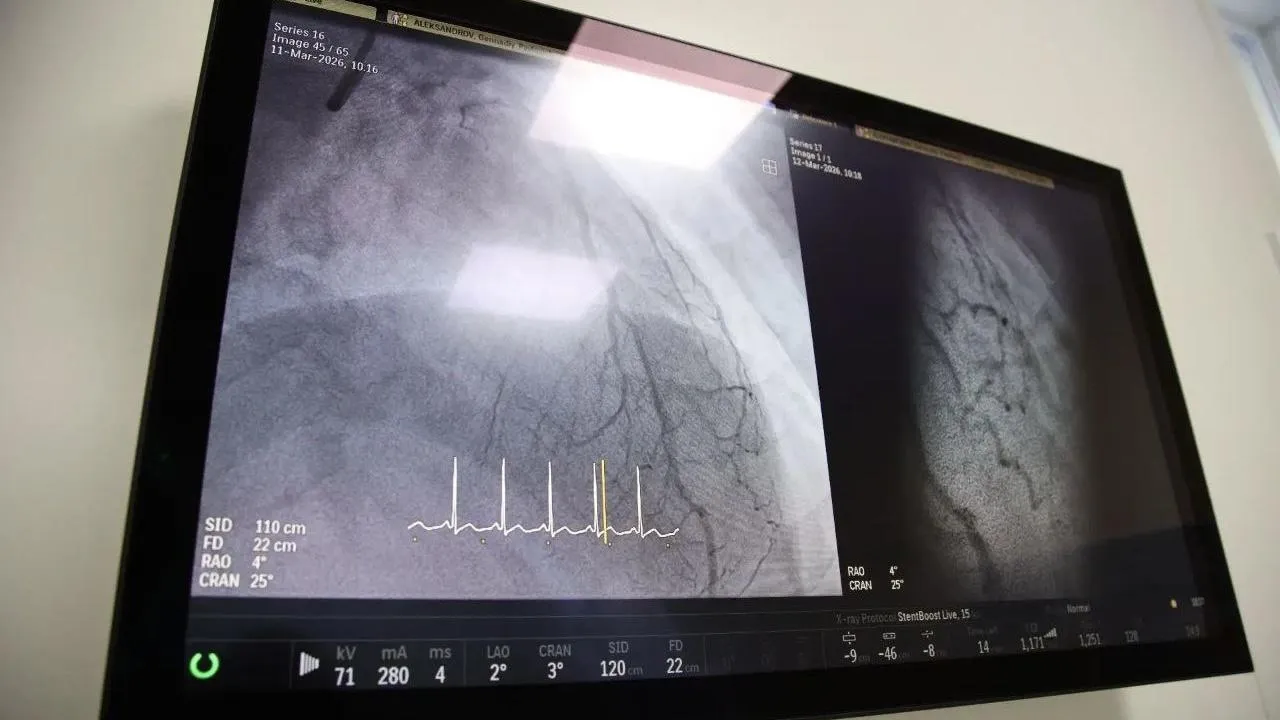

Воскресенские врачи установили стенты, не прерывая сердечно-легочной реанимацииМедики Воскресенской больницы спасли жизнь пациенту из Коломны с помощью уникальной операции на сердце. Так, 57-летнего мужчину в критическом состоянии час оперировали и одновременно проводили сердечно-легочную реанимацию.

Пациент поступил в сердечно-сосудистый центр в критическом состоянии. Из приемного покоя его сразу направили в операционную. Пациенту сделали экстренное стентирование коронарных артерий.

Благодаря профессионализму врачей и современному медицинскому оборудованию хирурги успешно имплантировали два новых стента и спасли мужчину в тяжелом состоянии.

Врачам помог новейший агиографический комплекс и метод оптической когерентной томографии. Оборудование появилось благодаря поручению губернатора Московской области Андрея Воробьева в рамках реализации нацпроекта «Продолжительная и активная жизнь».